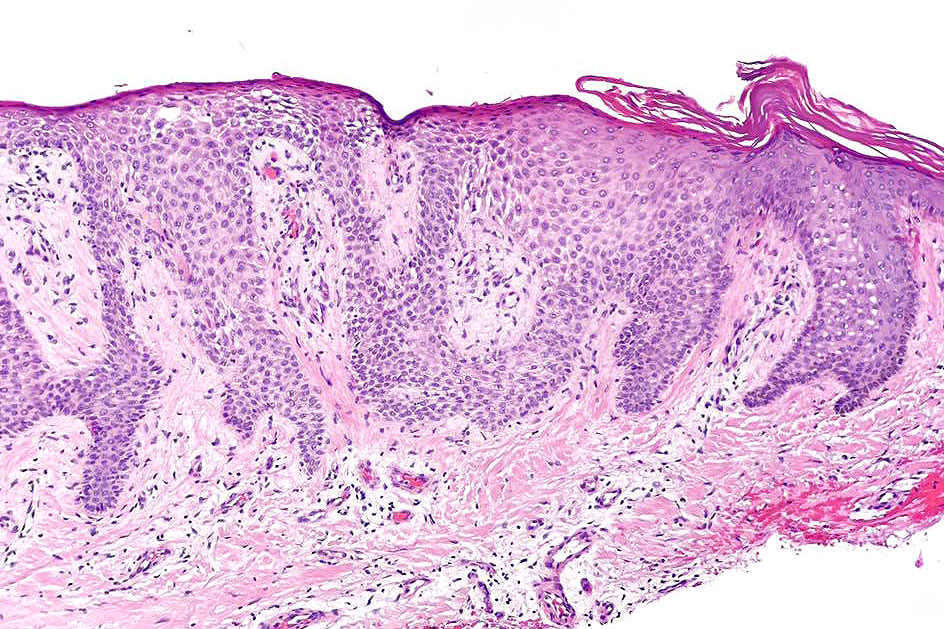

•Sharply demarcated acanthosis/psoriasiform hyperplasia; bland epithelium

•Fusion of rete ridges

•Cytoplasmic pallor or clear cell change; spongiosis sometimes present

•Characteristic intraepidermal adnexal epithelial sparing